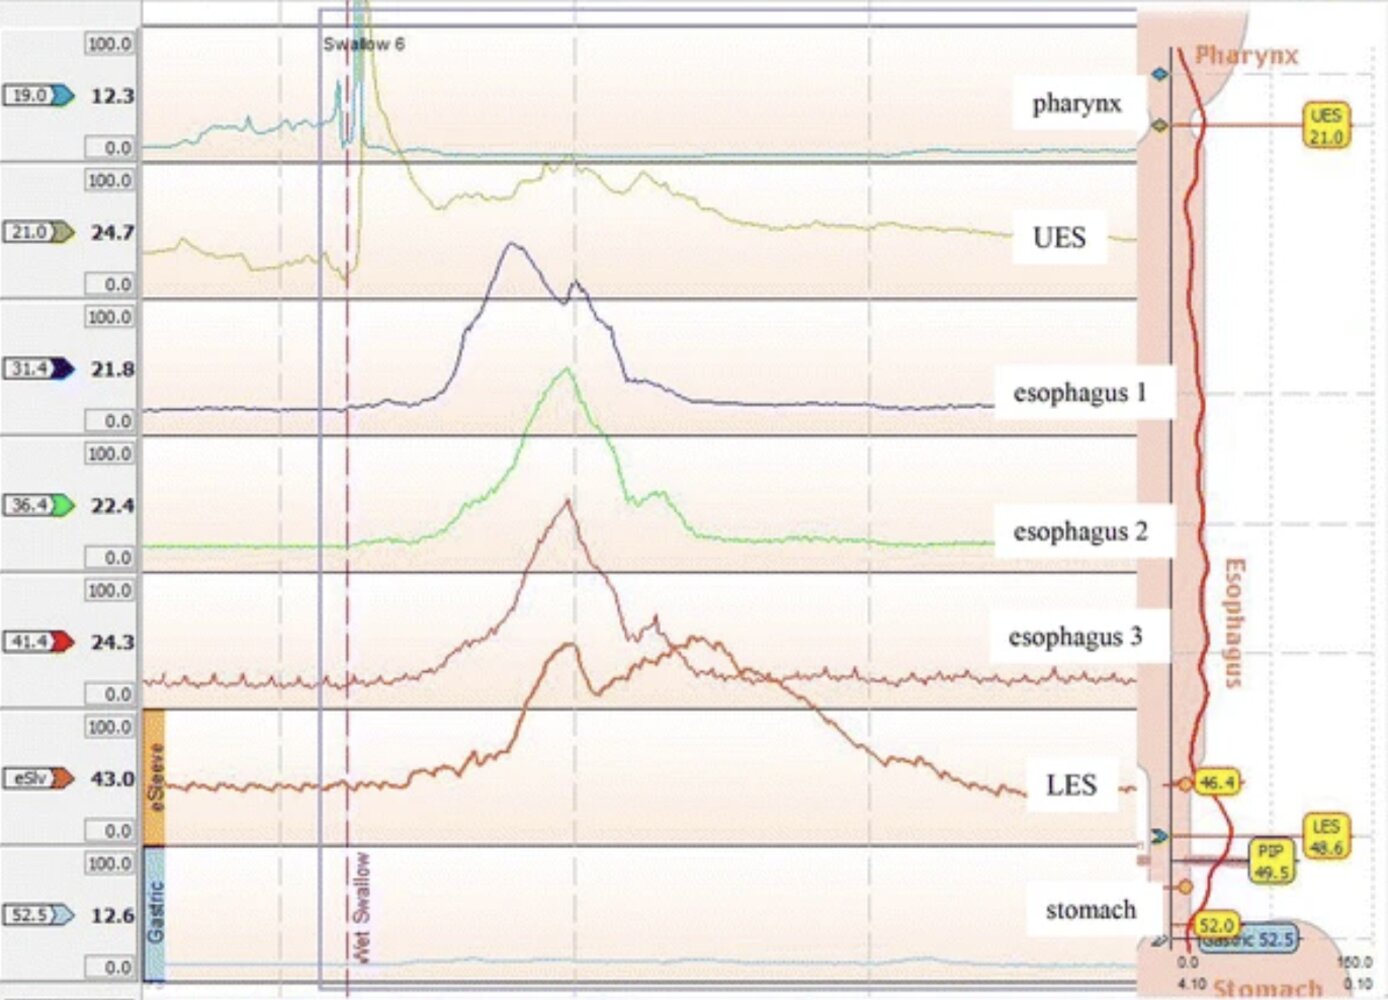

High-resolution esophageal manometry (HRM) [2][3][4]

• Indication: gold standard to confirm achalasia and determine subtype by measuring LES pressure and esophageal peristalsis

• Findings

• Absent or uncoordinated peristalsis in the lower two-thirds of the esophagus

• Impaired LES relaxation (i.e., incomplete or absent) with increased LES resting pressure [5]

• Possibly increased panesophageal pressure

High-resolution esophageal manometry [12]

• Distal contractile integral (DCI) < 5000 mm Hg/second/cm

• Distal latency (DL) ≄ 4.5 seconds

• ↑ LES relaxation pressure

• See ā€œAchalasia subtypes.ā€